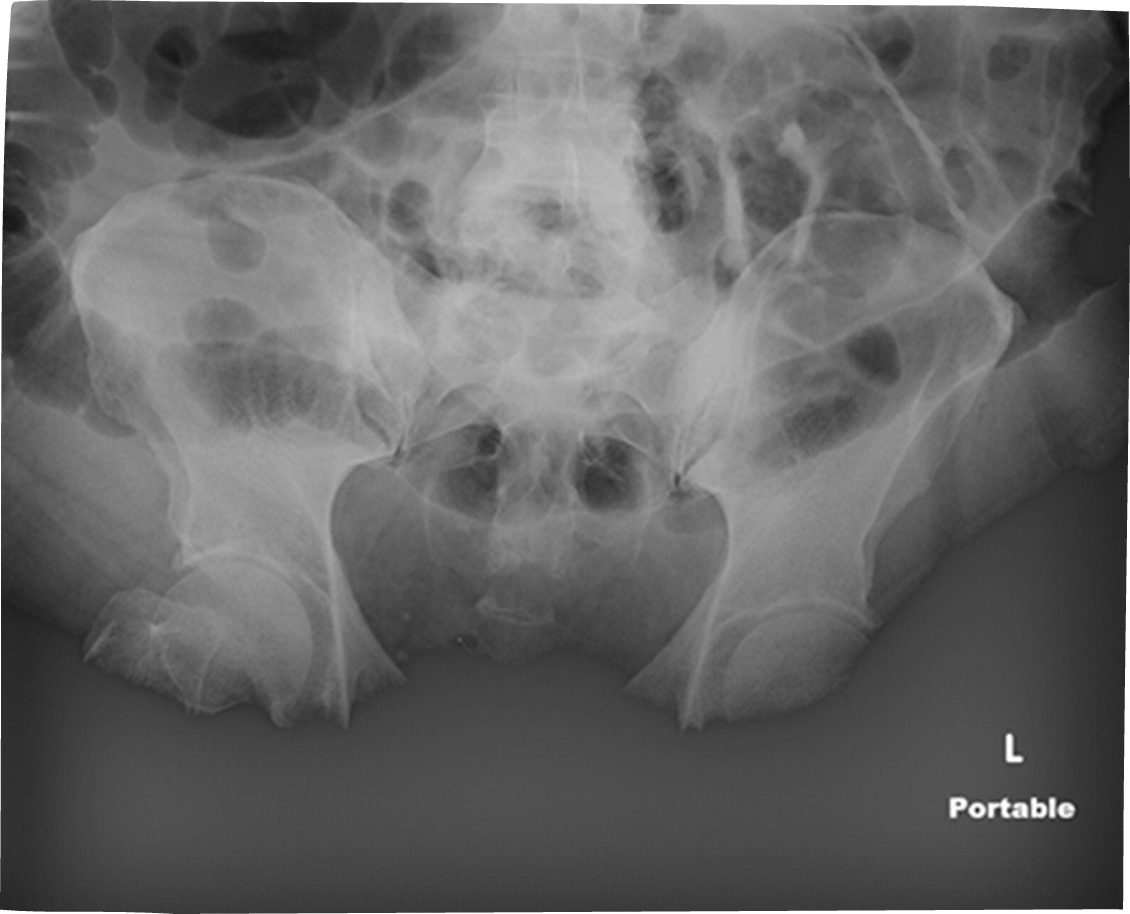

(Image shows saturation - Maybe Big Belly? )